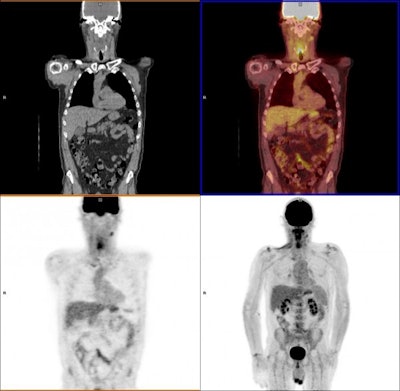

FDG-PET/CT is well-known for identifying both structural and metabolic abnormalities in tumors. One published meta-analysis reported that FDG-PET/CT achieved negative predictive values of 94% to 96% among head and neck squamous cell cancer patients after treatment.

Twelve weeks after their last cancer treatment, patients assigned to the planned neck dissection group were scanned using CT or MRI, while subjects in the experimental, surveillance group underwent PET/CT scans to assess the results of therapy.

Patients who had significant FDG uptake on PET/CT scans after 12 weeks of treatment were classified as having an incomplete nodal response, while mild or no FDG uptake in enlarged nodes or mild FDG uptake in normally sized nodes was considered an equivocal response. These patients subsequently underwent neck dissection. All other results were deemed complete responses to therapy.